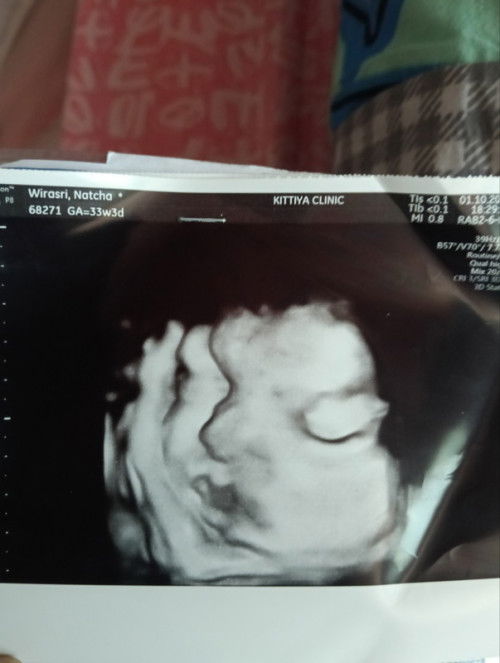

ขอสอบถามหน่อยค่ะ คุณแม่ท่านไหนที่มีประสบการณ์เป็นไทรอยด์ในช่วงตั้งครรภ์ คลอดด้วยวิธีไหนคะ พอดีมารู้ตัวว่าเป็นไทรอยด์ตอนท้องเพราะคุณหมอทักว่าคอโต พิไปตรงจเลือดปรากฏว่าเป็นไทรอยด์แต่ว่ายังไม่มีอาการมากค่ะ ยังไม่ตาโปน น้ำหนักก็ไม่บดในช่วงที่ท้องตอนนนี้น้ำหนักขึ้น14กิโลแล้วค่ะ ท้อง8เดือน คอที่โตพอไปอัลตร้าซาวด์กับหมอเฉพาะทางเขาบอกว่าต่อมไทรอยด์ไม่ได้โตค่ะ เท่ากันทั้ง2ข้างไม่มีข้างไหนบวมค่ะ ช่วยเเนะนำหน่อยค่ะพอดียิ่งใกล้คลอดยิ่งกลัวค่ะ มีพี่พยาบาลบอกว่าเป็นไทรอยด์อาจได้ผ่าคลอดแต่จะส่งไปโรงพยาบาลในเมืองเหมือนโรงพยาบาลที่ฝากอยู่รับไม่ไหวเหมือนมันอันตรายมากมั้ยคะแม่ไปหนูกลัว🥹🥹😢 # #ไทรอยด์ตอนท้อง